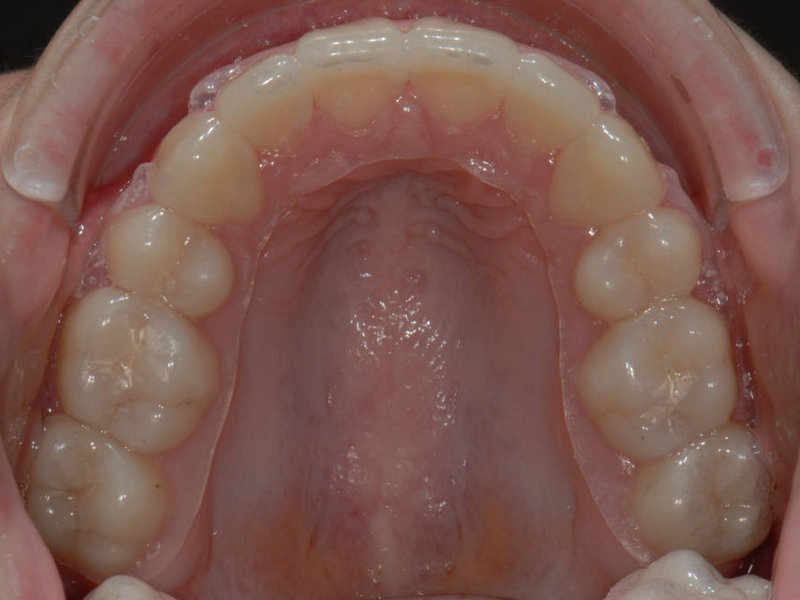

Essixskena (C)